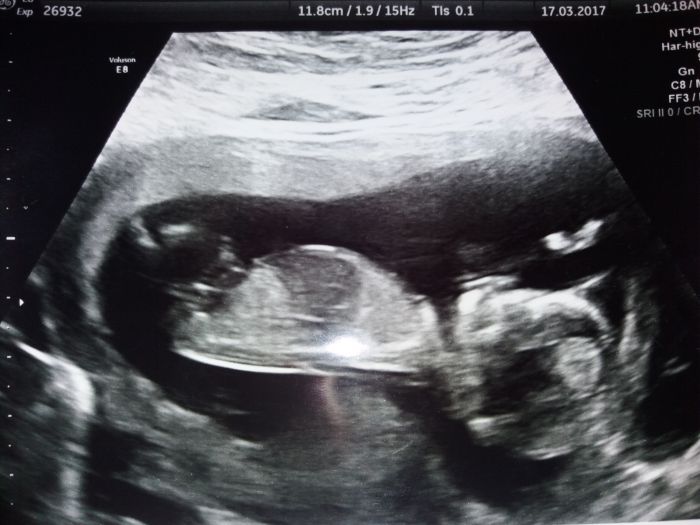

Tak ja mam screening uz take za sebou. Marci158,take mam termin 18.9. Na fotce ma mimi skoro stejne brisko jako to nase?. Mimco se pri kontrole taky mrskalo,dokonce stalo i na hlave?. Pry je vse ok a zatim to vypada na holcicku. Doma uz jednu 2r mame. Hezky den.

Tak ja mam screening uz take za sebou. Marci158,take mam termin 18.9. Na fotce ma mimi skoro stejne brisko jako to nase?. Mimco se pri kontrole taky mrskalo,dokonce stalo i na hlave?. Pry je vse ok a zatim to vypada na holcicku. Dima uz jednu 2r mame. Hezky den.

Tak ja mam screening uz take za sebou. Marci158,take mam termin 18.9. Na fotce ma mimi skoro stejne brisko jako to nase?. Mimco se pri kontrole taky mrskalo,dokonce stalo i na hlave?. Pry je vse ok a zatim to vypada na holcicku. Doma uz jednu 2r mame. Holky taky jste tak unavene? Ja se v noci tech 9 hod v klidu vyspim,s malou vstavame v 8,ale kol poledne uz ssm uplne ko?Hezky den.